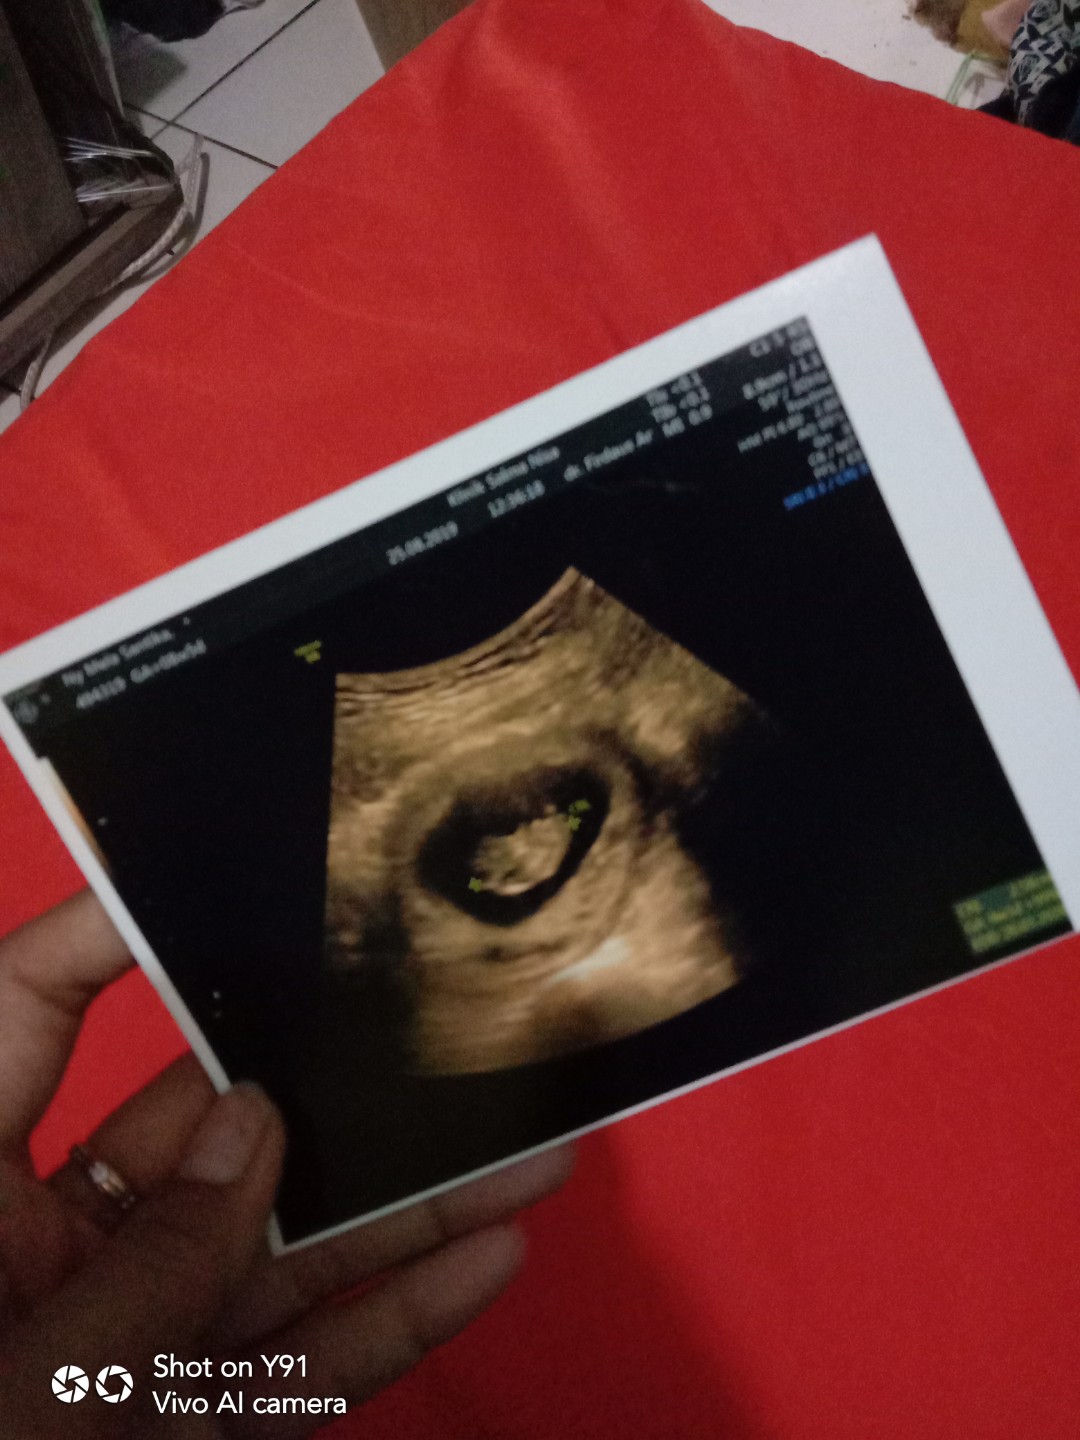

Bun,usia 6w gambar usg nya kygini normal ga sih Bun?? Tadi dokternya bilang, ga berkembang masa?? Disuruh balik lagi seminggu selanjutnya untuk di usg lagi

Itu bund hasil usg ku kemarin , katanya 8w 1h to masih bulat belum bentuk dedek .. aku awalnya kawatir tp yakin Sama yg d atas pasti beri yang terbaik. Aku jg ngk Tau ith normal apa engk

Sudah bagus itu Bun sudah ada kantong 6w,,yg sabar Bun dan tetep semangat yaa,, positif thinking terus dan banyak berdoa saja Klo nurut saya tunggu 2minggu aja baru usg ulang..

Saya 6w juga masih kantong janin Bun. Bukan gak berkembang sih tapi emang rata2 usia segitu masih kantong janin bun. Nanti balik 2 atau 3 Minggu lagi udah ada janin nya bun